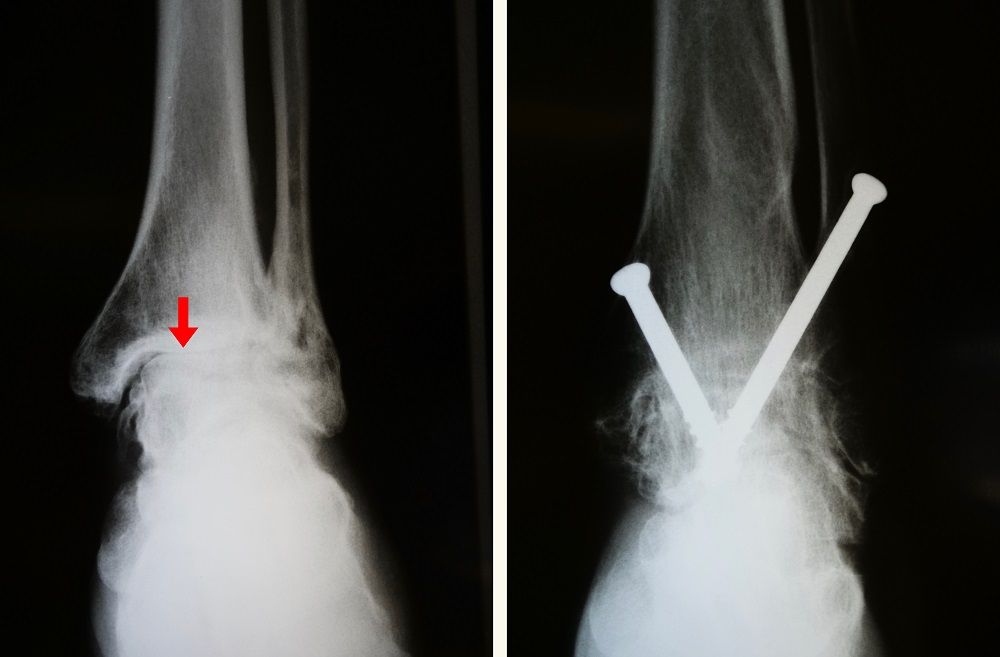

x-rays of ankle arthritis and arthrodesis (fusion)

(Left) X-rays show ankle arthritis. Joint spacing narrow (arrow) has resulted in bone rubbing on bone. (Right) A different arthritic ankle after treatment with arthrodesis. Screws are used to hold the bones in proper alignment until the fusion is complete.

Images courtesy of Stuart J. Fischer, MD, FAAOS

Arthrodesis (fusion). Arthrodesis fuses the bones of the joint completely, making one continuous bone out of two or more bones. The goal of the procedure is to reduce pain by eliminating motion in the arthritic joint.

During arthrodesis, the surgeon removes the damaged cartilage and then uses pins, plates and screws, or rods to fix the joint in a permanent position. Over time, the bones fuse, or grow together, just like two ends of a broken bone grow together as it heals. Since the bones no longer move, there should not be any more pain.